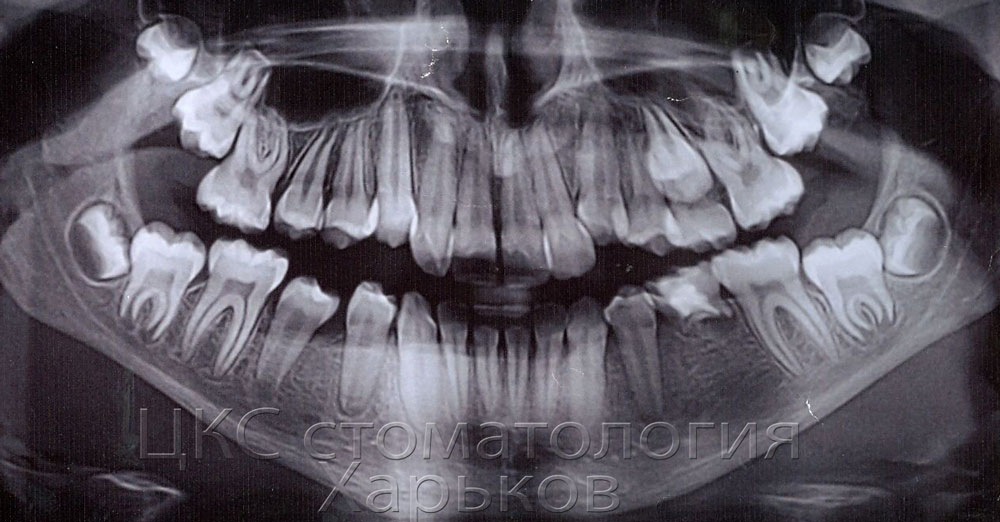

Отсутствие зачатков

Отсутствие зачатков 109 фото